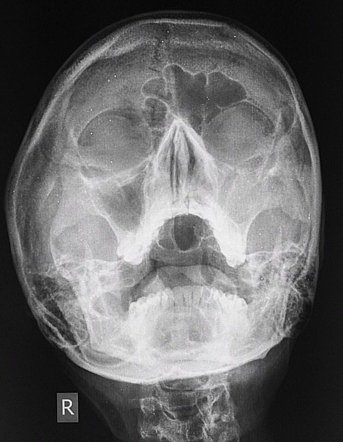

• Radiologia Digital.

Radiologia Digital.

F. Mouyens creó el primer sistema de radiología digital directa que produce imágenes de calidad. Un detector de pantalla convierte directamente el patrón de energía de rayos X en señales eléctricas.